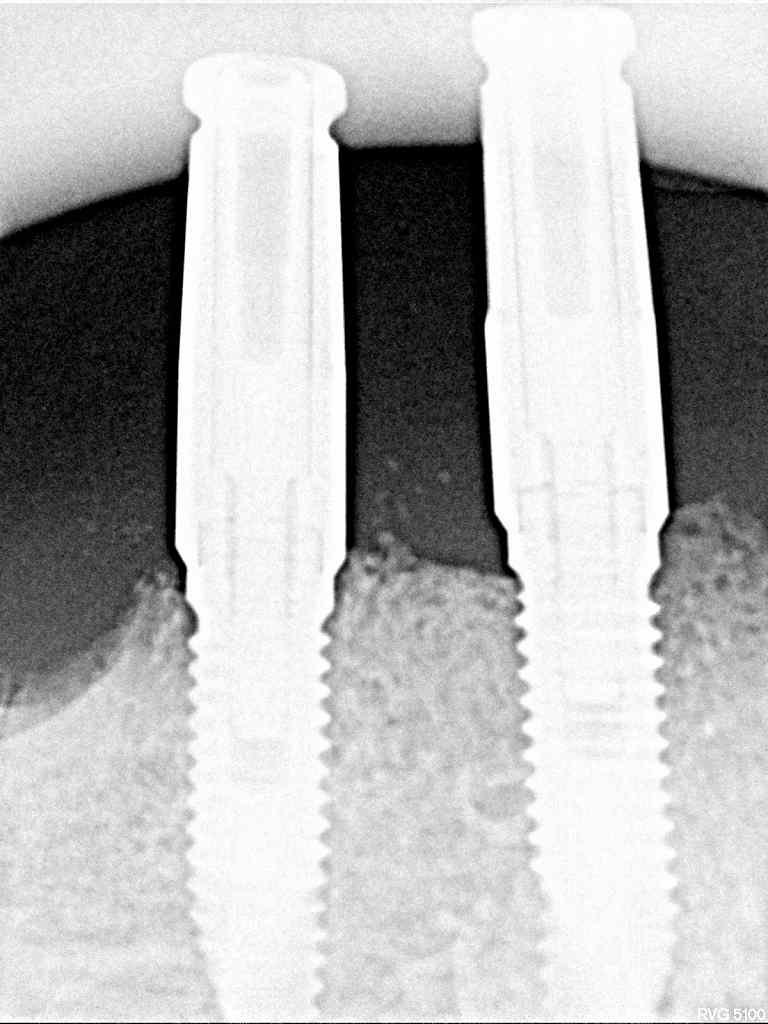

インプラント埋入時になります

3本とも4mmの13mmというインプラントを埋入

インプラントはオペ時に5本入れていることになります